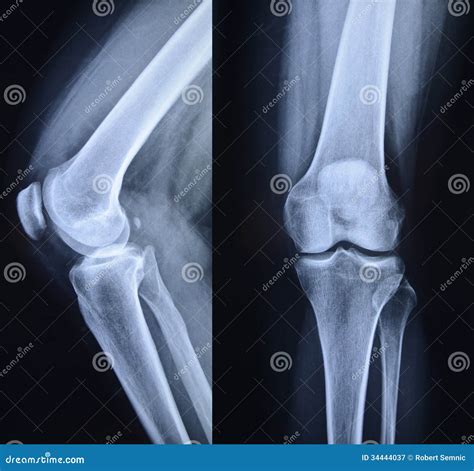

Understanding Knee X-rays

Knee X-rays are a type of medical imaging that uses low doses of radiation to produce images of the knee joint. These images help doctors identify various conditions, including fractures, dislocations, and degenerative changes. The process is non-invasive and relatively quick, making it a preferred method for initial knee evaluations.

Interpreting Healthy Knee X-rays

Interpreting knee X-rays requires a trained eye. Here are some key features that radiologists look for in Healthy Knee X-rays:

• Bone Structure: The bones of the knee, including the femur, tibia, and patella, should appear smooth and intact without any fractures or deformities.

• Joint Space: The space between the bones should be uniform and not narrowed, which can indicate wear and tear or arthritis.

• Soft Tissue: While X-rays primarily show bone, the soft tissue around the knee should appear normal without any signs of swelling or inflammation.

• Alignment: The knee joint should be properly aligned, with no signs of dislocation or misalignment.